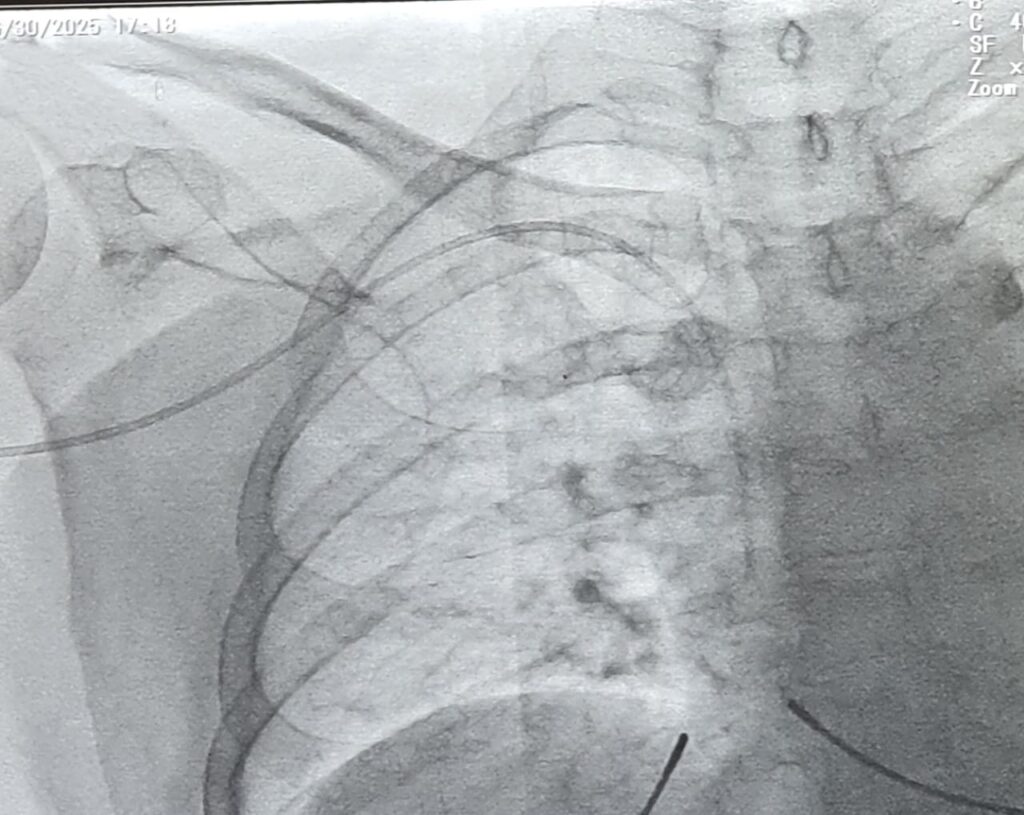

Peripherally Inserted Central Catheter

Expert PICC line insertion and precision-guided vascular access services available at NIRS.